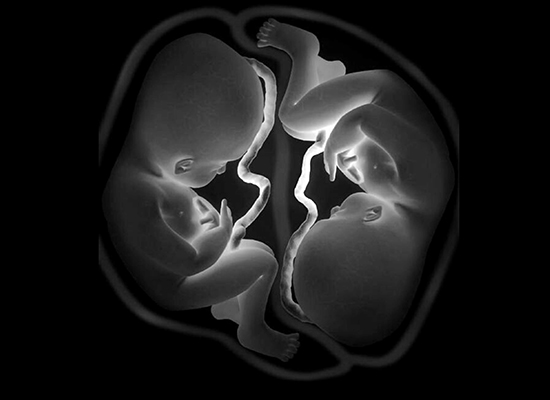

Multiple pregnancies

The condition where a woman is carrying two or more fetuses is called multiple pregnancies. Women with multiple pregnancies may have more severe morning sickness, greater breast tenderness, more weight gain. They also have a higher risk of developing preeclampsia, gestational diabetes, and going into pre term labor. Their diet and activity levels also need to be monitored, so as to ensure optimum growth of the fetuses.

Women with multiple pregnancies will need more frequent visits to the obstetrician. From the second trimester on wards they will also need more frequent scans.